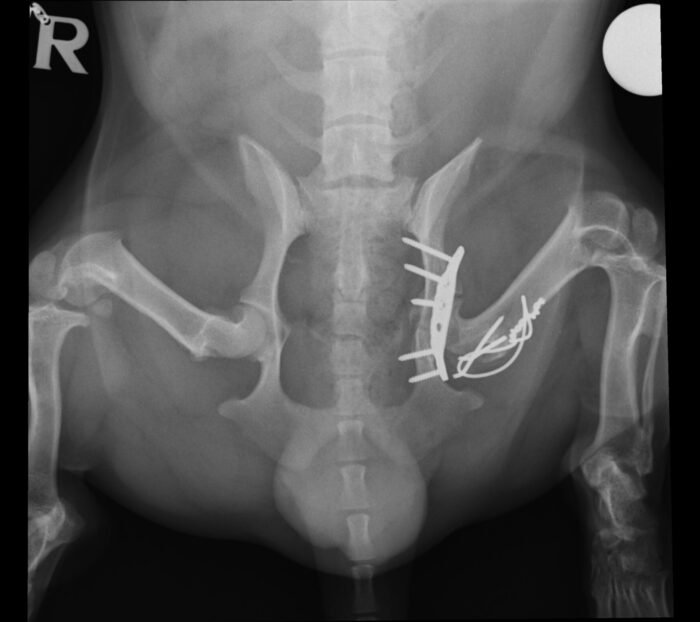

As always with pelvic surgery, the procedure was complex and challenging. To gain proper access to the fractured acetabulum, we had to cut and reflect a section of femoral bone with it’s attached gluteal muscle. This step allowed clear visualisation of the break. The sciatic nerve was carefully identified and protected throughout the procedure – a critical part of preventing long-term neurological damage.

Once the fracture site was fully exposed, the bone fragments were meticulously realigned to restore the smooth surface of the joint. A plate and screws were applied to hold everything securely in place. Finally, the top of the femur was pinned back into position, restoring the anatomy of the hip. The surgical wounds were then closed, and Dozer began his recovery.

Six weeks after surgery, follow-up X-rays brought welcome news. The implants remained stable, and the fracture was healing well. The careful reconstruction had held.